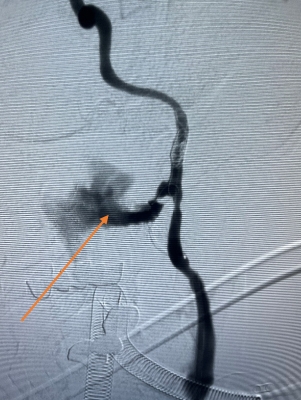

快速闭塞血管后无出血

后交通动脉开放 代偿左侧大脑中动脉供血

“患者左侧颈内动脉后交通动脉粗大,假性动脉近远端已经发生夹层改变。”手术团队凭借丰富的经验,果断决策闭塞左侧颈内动脉,选择大而长的弹簧圈在假性动脉瘤近远端闭塞颈内动脉,成功止住出血。取出咽喉部压迫棉片及棉条均无活动性出血,继续输血、输血浆,予以抗休克治疗。全脑血管造影显示,后交通动脉代偿良好,左侧大脑中动脉血流速度正常,眼动脉显影良好,患者的生命体征逐步恢复正常。见患者情况逐渐平稳,所有人都松了一口气。